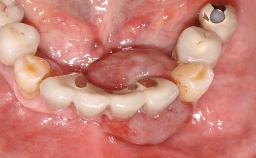

Excess Cement Resulting in Peri-implant Infection Presenting as a Draining Sinus Tract

Biological complications caused by undetected cement residue have been receiving much attention. Excess cement might be responsible not only for rapidly developing of peri-implantitis, but also for delayed or chronic manifestations of the disease many years after cementation (Wilson 2009; Linkevicius and coworkers 2013). Invitro and clinical studies have shown that it is very difficult or even impossible to completely clean up excess cement at subgingival margins, so popular in cemented restorations (Agar and coworkers 1997; Linkevicius and coworkers 2011, 2012). Possible outcomes of biological complications due to excess cement range from temporary inflammation of the peri-implant soft tissues without any serious esthetic and functional consequences all the way to implant loss. This report describes a case of peri-implantitis caused by residual cement; as well as the management and quite unusual resolution of the complication. The patient presented in 2009 with a draining sinus tract, tenderness on chewing, and tissue contact above the implant-supported restoration. The implant had been restored approximately three years before.